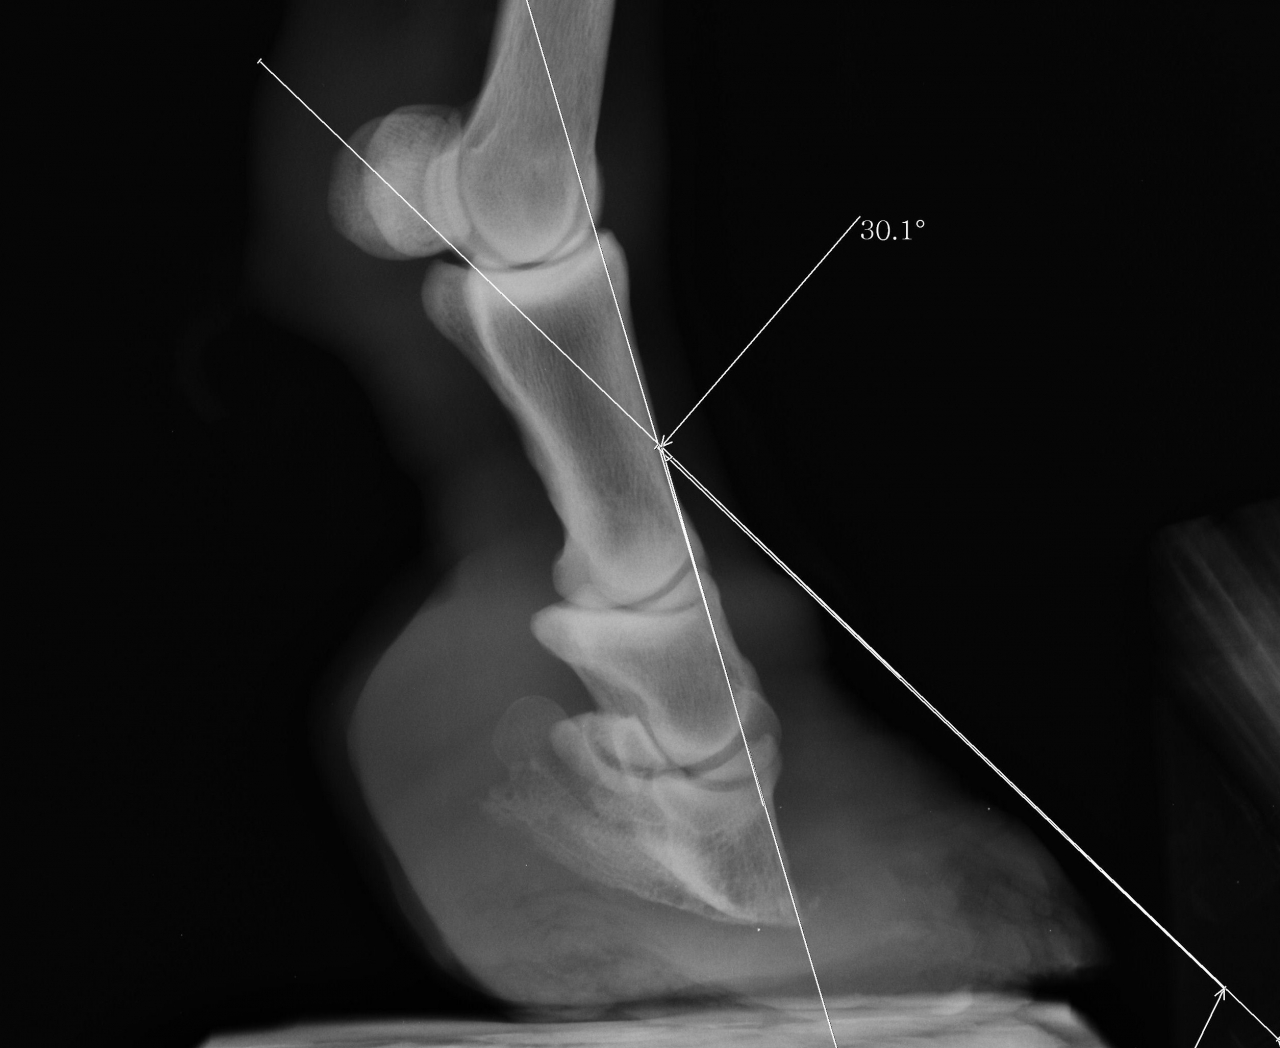

DéconnectéDire merci | Bonjour, Je viens vers vous pour ma vieille ponette (âgée aux alentours de 30 ans) que j’ai recueillie en février 2014 qui est atteinte du syndrome de cushing et a une fourbure chronique avec bascule de la 3ème phalange de 30° pour les 2 antérieurs. En juin dernier (8 juin 2015), lors de son dernier parage alors que seule la pince a été rognée et les talons abaissés d’un ½ cm, elle est tombée dans une souffrance terrible, à rester couchée et à ne se relever que pour manger et faire ses crottins, j’ai cru la perdre. C’est cela qui m’a poussé à faire des radios (qui ont été faites donc 3 semaines après le parage) ; Les radios ont révélé une bascule de la 3ème phalange de 30° sur les 2 antérieurs. Bien sûr pour les vétos qui la suivent, la seule proposition a été l’euthanasie mais ma ponette s’est battue car elle a envie de vivre et moi je me bats à ses côtés. Elle a commencé à aller mieux lorsque ses pieds ont commencé à repousser après 2 mois vers fin juillet début aout ; au lieu d’une souffrance continue, elle a mal seulement lorsqu’elle se déplace (elle se déplace très peu, tout son petit paddock est recouvert d’un épais tapis de paille ; elle a un régime adapté avec plusieurs rations réparties sur la journée composées d’un mélange de foin haché et granulés de paille réhydratés de sorte que le taux de sucres ne dépasse pas 5%). Le maréchal qui la suivait, pareur naturel et ancien maréchal, m’a lâché en aout car il n’a pas voulu admettre, comme beaucoup de maréchaux ferrants que j’ai contactés pour avoir des avis, que ma ponette ne retrouverait pas un fonctionnement normal des pieds et que le mieux pour elle était de lui laisser du pied et lui faire seulement un parage « antalgique » adapté à son cas, de façon à lui permettre de continuer sa petite vie avec le moins de douleur possible. Lui abaisser les talons, lui faire un parage type parage naturel ne l’entrainerait que vers des douleurs insupportables avec le risque qu’elle succombe à ces douleurs. Je me suis battue depuis aout pour trouver un maréchal compétent qui veuille bien se déplacer et un maréchal a enfin accepté de venir la semaine prochaine ; mais pendant ses 4 derniers mois les pieds de ma ponette ont énormément poussé et sont en babouche mais étonnamment elle n’a pas plus mal lorsqu’elle se déplace que les mois précédents lorsque ses pieds n’avaient pas encore atteint ce stade critique en babouche (Croyez moi ça me rend folle d’en être arrivé là, tout aurait pu être tellement plus simple et occasionner moins de souffrance si le pareur naturel en aout avait accepté de se contenter de faire un entretien des pieds…). Je voulais préciser que lorsque ma ponette se déplace, elle prend appui sur la pince en arquant les membres (elle s’est toujours déplacée ainsi quelque soit la taille de ses pieds). Bien sûr maintenant avec ses pieds en babouche, elle a les glomes proches du sol et c’est son talon qui lui sert de voute plantaire, la sole remontant vers l’avant presque perpendiculairement au sol… Je me pose la question de savoir comment se positionne la 3ème phalange maintenant dan un tel pied. En fait, je me pose beaucoup de questions car j’ai peur, très peur que l’intervention de la semaine prochaine sur ses pieds, même si le parage sera léger car il est hors de question de redonner en une seule intervention, une forme normale à ses pieds, n’entraine à nouveau mon petit bout de ponette vers une souffrance terrible, dont je sais cette fois qu’elle ne se remettra pas…elle me le fait comprendre à sa manière, à savoir que pour qu’elle me donne un de ses antérieurs, je dois négocier bien 10 min, cela lui engendre un stress important avec accélération de la respiration et bien sûr je dois lui prendre et aussitôt le reposer, juste le temps de lui déposer une compresse imbibée de liqueur de villatte car la corne sous ses pieds pourrie. Peut-on la laisser avec ses pieds en babouche pour éviter le risque de la replonger dans une douleur insupportable en touchant même si peu que ce soit à ses pieds ? Y-t-il vraiment un risque qu’elle replonge dans la douleur si on se contente simplement de rogner la partie en babouche ? Voilà, je vous remercie vraiment par avance pour votre aide, vos conseils et vos témoignages. Je vous joins des photos et radios de ses pieds. Désolée du pavé… radio antérieur droit ![]() radio antérieur gauche ![]() photos après parage juin 2015 ![]() ![]() photos septembre 2015 ![]() photos aujourd'hui ![]() ![]() |

| Dire merci | Quand on regarde les radios, le confort s'explique par une position alors "normale" des phalanges, donc moins de tension dans les tendons etc... mais ça fait mal au bide à voir... sauf que le mal au bide est du côté de l'humain et le "confort" est du côté poney... |

Déconnecté | Si elle est bien en babouches, c'est parce que sa phalange se trouve à la "bonne place" pour le coup...et donc elle est bien. Il ne faut pas, enfin plutôt il ne faut plus chercher à redresser tout ça. Ne pas oublier qu'il y a sans doute de l'arthrose la dedans. Je pense que le maréchal se contentera ou devra se contenter de rogner ce qui est en trop, et donner des conseils pour nettoyer si besoin est (genre bains de pied dans un pediluve par ex, la faire marcher dedans). Pour ma part je ne trouve pas qu'elle aille contre la santé de la ponette, s'il fallait piquer un cheval à chaque crise, on serait pas rendu. Elle a les moyens de la soulager, elle fait tout ce qu'elle peut (y' en a pas beaucoup qui y iraient jusque-là) et si la ponette a souffert à ce point...c'est parce qu'elle a eu un parage raté, et à 30 balais avec une telle bascule, ça pardonne pas. Il faut la soulager autant que possible, mais le jour ou on ne pourra plus rien faire, même son moral semble bon, il ne faut pas aller plus loin. Même si on souhaite gagner 3 jours, ou 3 semaines, cela peut être 3 jours ou 3 semaines d'enfer. |

DéconnectéDire merci | Si elle est bien en babouches, c'est parce que sa phalange se trouve à la "bonne place" pour le coup...et donc elle est bien. Phoeb, pouvez vous préciser ? Vous voulez dire que la 3ème phalange est parallèle au sol ? par rapport à cette question, le maréchal qui doit venir n'a pas su répondre et une des vétos qui la suit m'a dit que la 3ème phalange était comme sur la radio en alignement avec les phalanges 1 et 2 et piquait toujours vers le sol dans son pied en babouche. |

Déconnecté | Lara129: oui c'est ça, phalange parallèle au sol. Mais attention, c'est juste une idée, enfin plutôt une interrogation à étudier avec le maréchal. La pointe de la phalange dans la sole ça fait une grosse pression sur un endroit très réduit donc forcément douloureux. Et la position de la ponette influant sur la forme de la pousse des pieds pour se soulager elle a peut être (sûrement?) trouvé un moyen de repartir la pression sur une plus grande surface. Alors certes ça pourrit c'est moche et ça fait maltraité, mais si elle mieux ainsi qu'avec des pieds normaux à son âge, je pense que c'est le mieux. Tu as fait endorment de choses pour elle en tout cas, je tiens à te dire bravo, j'admire vraiment tout ce que tu as fait pour elle, c'est un geste magnifique. Et tu n'as pas à t'en vouloir d'avoir fait tel ou traitement, on ne peut jamais savoir ce qui peut arriver à l'avance. |